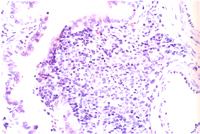

組織病變: 肺臟部份區域可見圍小支氣管及圍血管周圍淋巴組織增生(圖3),這些細胞以淋 巴球及少量巨噬細胞和漿細胞為主(圖4)。

其它病變可見第二型肺泡細胞增生,小支氣管上皮細胞肥大增生,小支氣管擴張, 肺泡間隔淋巴球及漿細胞等浸潤。

黴漿菌症為大小鼠首要病原,而且可藉由空氣或接觸感染,一旦發生,其難滅絕。 黴漿菌有20多種血清型,而一般會造成人或囓齒類感染為:M. collis : 非致病性,存在於大小鼠之鼻咽部及結膜,亦有報告指出會造成生殖道感染。 M. arthritidis : 大鼠關節炎。 M. neurolyticum : 小鼠旋轉病。 M. pulmonis : 鼠類及兔子重要呼吸道傳染性病原。為大小鼠首要呼吸道病原其鑑別診斷見表一。 M. pneumoniae : 人類非典型肺炎。 M. hominis : 人類婦女生殖道感染。 而人鼠之間不同的黴漿菌亞型,一般而言並不會互相感染,亦即並非人畜共通疾病。 大鼠對黴漿菌較敏感,而報告指出不同的菌種中以上M. pulmonis 具顯著呼吸道致病性。患鼠出現體重減輕、呼吸困難或呼吸道震顫聲。一旦環境中氨濃度高過25ppm以上或病毒(Sendai,MHV)合併感染則會加重黴漿菌感染之疫情。感染途徑可經空氣傳播、子宮感染及接觸等方式。臨床症狀有時在感染後 3~6個月才出現。病變一般呈不顯性或輕度症狀,鼻腔、呼吸道、中耳、子宮是檢查重點。肉眼可見化膿性鼻炎、肺前腹端肝變、支氣管擴張、肺膿瘍或中耳炎。組織相特徵為呼吸道上皮細胞扁平化生,纖毛消失,感染鼻腔黏膜及咽上皮細胞出現聚合細胞(syncytia),肺臟圍支氣管及圍血管周圍淋巴球及漿細胞增生,慢性小支氣管炎,小支氣管擴張,化膿性中耳炎。

而大鼠肺臟之支氣管圍管現象是以淋巴球為主,而小鼠則以漿細胞為主,此點為其 不同。裸鼠鼻腔接種M. pulmonis會發病造成關節炎,一般小鼠則不會。此為證明黴漿菌感染方法之一。